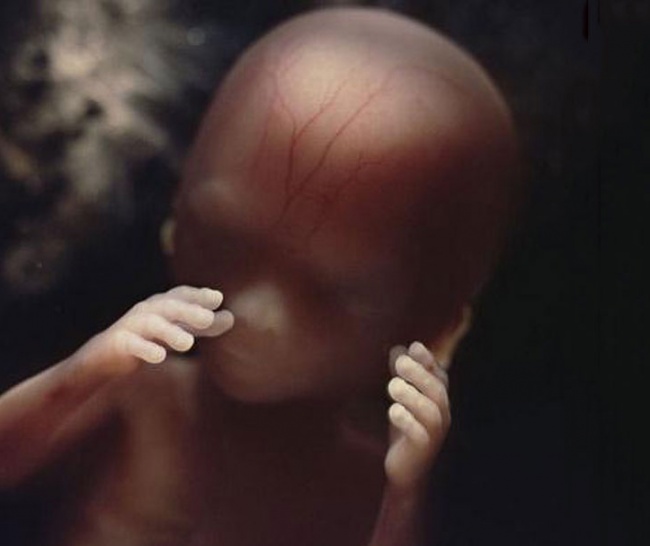

Las manos del embrión en la semana 19.